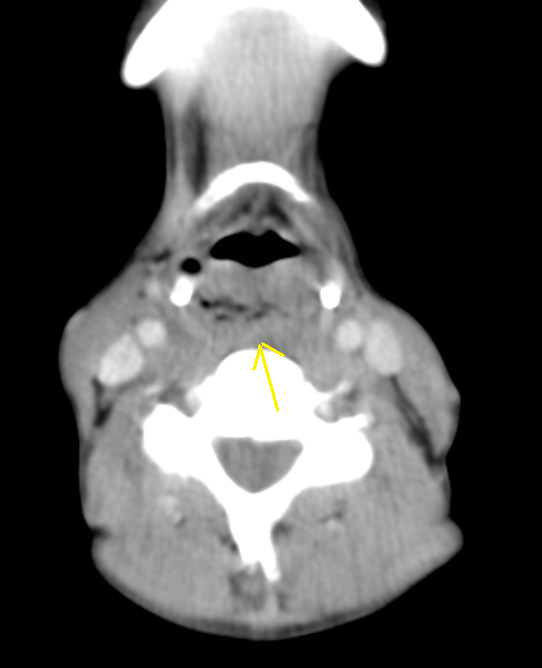

CT scan showing the post cricoid carcinoma extending down to upper

CT scan showing the post cricoid carcinoma extending down to upper Ca Postcricoid Postcricoid carcinoma is a rare but aggressive type of hypopharyngeal carcinoma with poor. imrt using the concomitant boost technique may be advantageous to irradiate postcricoid carcinomas in. the postcricoid region, pyriform sinus, and posterior hypopharyngeal wall comprise the hypopharynx. the lesion extends in the postcricoid hypopharynx and reaches the lower margin of the cricoid cartilage. Signs and. Ca Postcricoid.